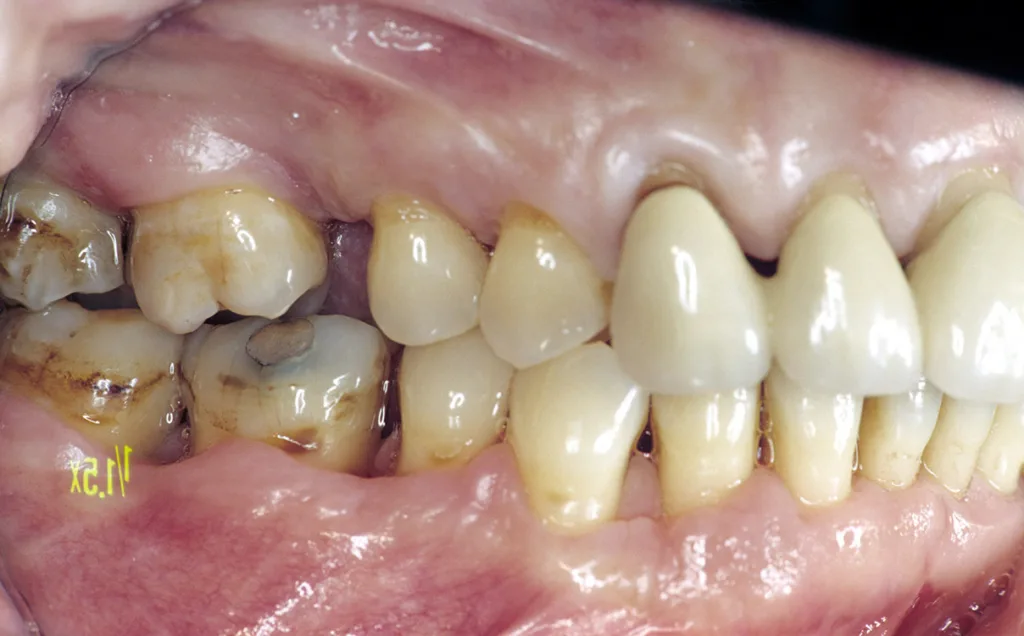

- Anatomie: Behandelte fortgeschrittene Parodontalerkrankungen sind klinisch stabil, zeigen aber in den implantatrelevanten anatomischen Knochenabschnitten (bukkale Lamellen, interapproximales Septum) weitere Abbauvorgänge durch Entzündung (Abb. 1 und 2) [1].

- Funktion: Durch Zahnverlust oder Parodontitis entstehen funktionsbedingt Zahnwanderungen, die häufig mit Verlust der Front-Eckzahn-Führung einhergehen und in einer Gruppenführung mit alters- und gebrauchsbezogener Bisssenkung resultieren [2].

Daraus resultiert ein zweizeitiges Vorgehen mit (i) Entfernung prognostisch unsicherer Zähne, (ii) parodontaler Zieltherapie zur Sicherung des Restzahnbestandes, ergänzt durch (iii) mikrochirurgische Revision tiefer Resttaschen vor Implantation zum weiteren Entzündungsschutz (Abb. 3 und 4). Die Implantatplanung bleibt vorläufig. Ein definitiver Kostenvoranschlag wird erst nach funktioneller Entlastung und digitaler Beurteilung der Implantatknochenanatomie erstellt.